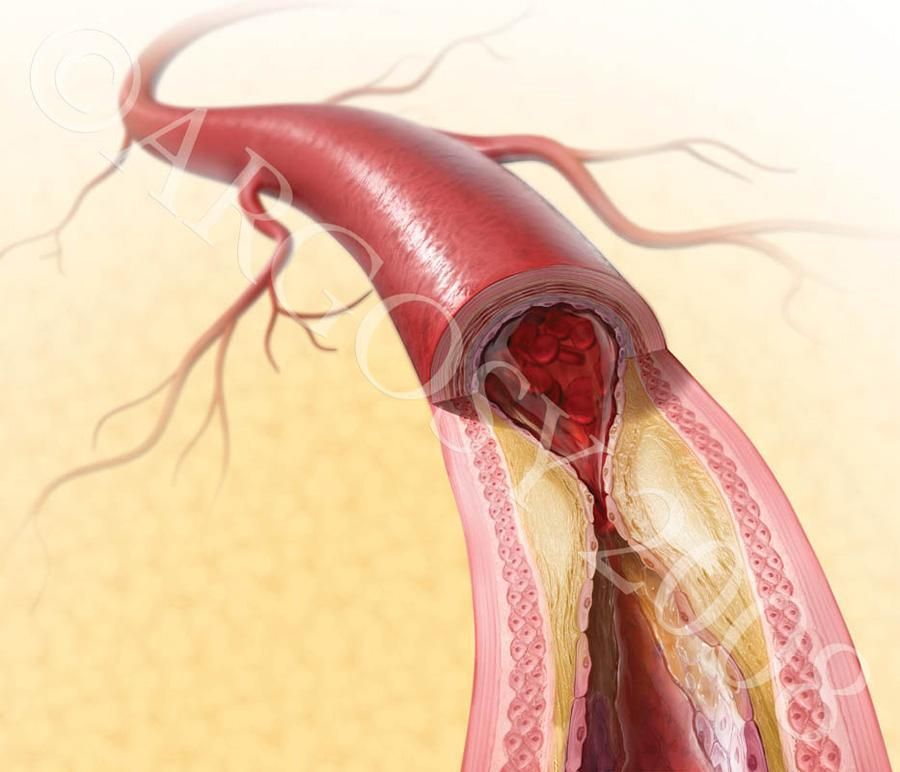

В 80% случаев причина носит СОСУДИСТЫЙ характер. Как было объяснено выше, в случае нарушения притока крови к половому члену, НАСТУПАЕТ ЭРЕКТИЛЬНАЯ ДИСФУНКЦИЯ. Основной причиной снижения притока крови служит сужение просвета приводящих артерии в результате атеросклеротического процесса в стенке артерии.

В случае наличия сосудистой причины эректильной дисфункции, виагра не устраняет поражения в артериях, кровоснабжающих кавернозные тела полового члена, а усиливают приток крови в результате расслабления мышц, в которых проходят мелкие кровеносные сосуды. Таким образом, не влияя на причину сосудистой импотенции, виагра лишь косвенным путем улучшает приток крови к половому члену.

После прокола артерии на бедре, в просвет сосуда вводится специальный зонд катетер, который подводится прицельно к артериям, кровоснабжающим половой член. После диагностики артерии и обнаружения сужения, в зону поражения артерии подводится миниатюрный баллонный катетер и сужение устраняется после раздувания баллончика. После сдувания и удаления баллона, на месте расширенного участка артерии ставится специальный каркас, который закрепляет результат и удерживает просвет артерии в раскрытом состоянии, нормализуя таким образом кровоток через расширенный и протезированный участок артерии. Указанная операция делается без общего наркоза и разрезов, только под местной анестезией с помощью маленького прокола (2-3мм) в бедренной артерии. В результате такого неинвазивного вмешательства нормализуется кровоток и, соответственно, нивелируется сосудистая причина эректильной дисфункции.